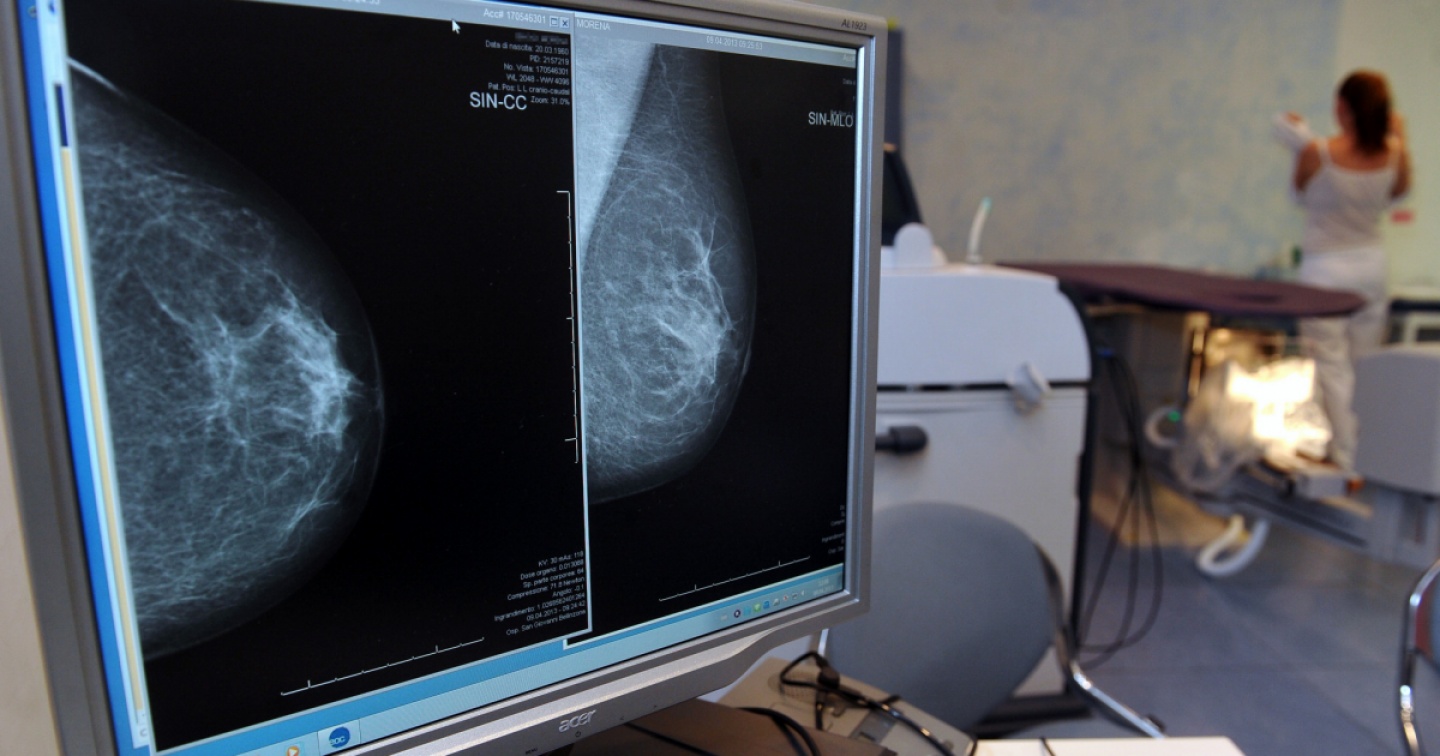

Ricercatori dell’Università di Basilea hanno acquisito nuove nozioni sul trattamento del cancro al seno. Sono riusciti a convertire cioè le cellule cancerogene in tipi di cellule meno dannose.

Le cellule tumorali hanno peculiarità simili a quelle delle cellule staminali e sono molto adattabili. Il team di ricerca guidato dallo scienziato biomedico Mohamed Bentires-Alj ha quindi sperimentato la possibilità di far maturare artificialmente le cellule del cancro al seno e di convertirle in un tipo di cellula normale. Questo procedimento denominato differenziazione è già utilizzato con successo nel trattamento della leucemia (cancro del sangue) ma non ancora nei tumori solidi.

Gli scienziati basilesi sono ora riusciti a utilizzare la differenziazione per trattare un cancro al seno triplo negativo. Si tratta di un tipo di neoplasia particolarmente aggressiva e relativamente "poco compresa", ha precisato Mohamed Bentires-Alj all’agenzia di notizie Keystone-Ats: "Con questa ricerca abbiamo trovato il meccanismo per trasformare le cellule tumorali aggressive in modo che diventino simili alle cellule normali", ha spiegato.

I risultati ottenuti aprono ora nuove strade per il trattamento del cancro al seno triplo negativo, che costituisce il 15-20% circa di tutti i cancri della mammella e colpisce in genere donne giovani, spesso sotto i 50 anni. Il tumore del seno triplo negativo deve il proprio nome al fatto che nessuno dei tre bersagli molecolari contro i quali esistono trattamenti mirati (recettore degli estrogeni, recettore del progesterone ed espressione di Her-2 aumentata) si riscontrano sulle sue cellule.